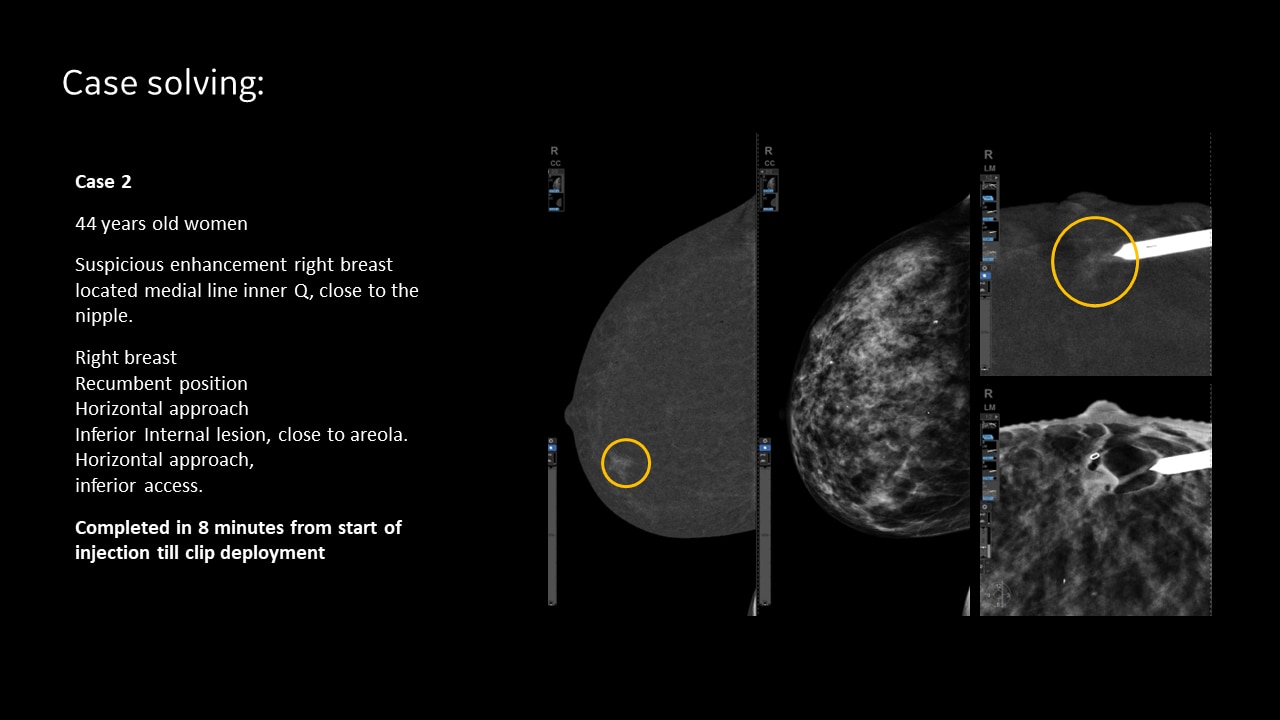

SEE AND BIOPSY WHAT MATTERS

Serena Bright™

Contrast-guided biopsy solution

Utilizes contrast-spectral mammography to clearly target and biopsy lesions without leaving the mammography suite.